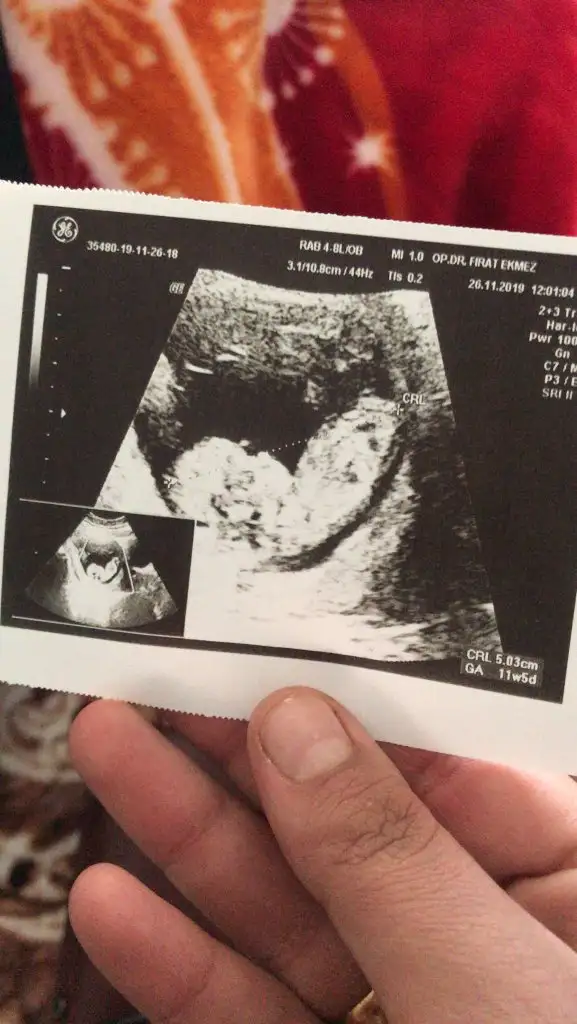

Nub görünmüyor boyutlu olmayan usg paylaşırmısınızMerhaba, bende 11 haftadayim. Tahmin edebilir misiniz?Eki Görüntüle 2558732

Usg 10+5 hafta 12 haftada paylaşa bilirsinizMaalesef doktorum sadece boyutlu usg verdi bize